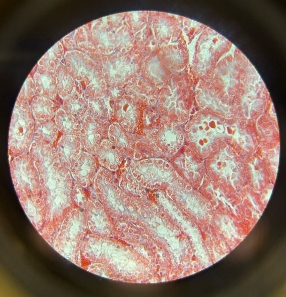

Cardiac Muscle

Cardiac Muscle

Cardiac Muscle

Cardiac Muscle

Cardiac Muscle